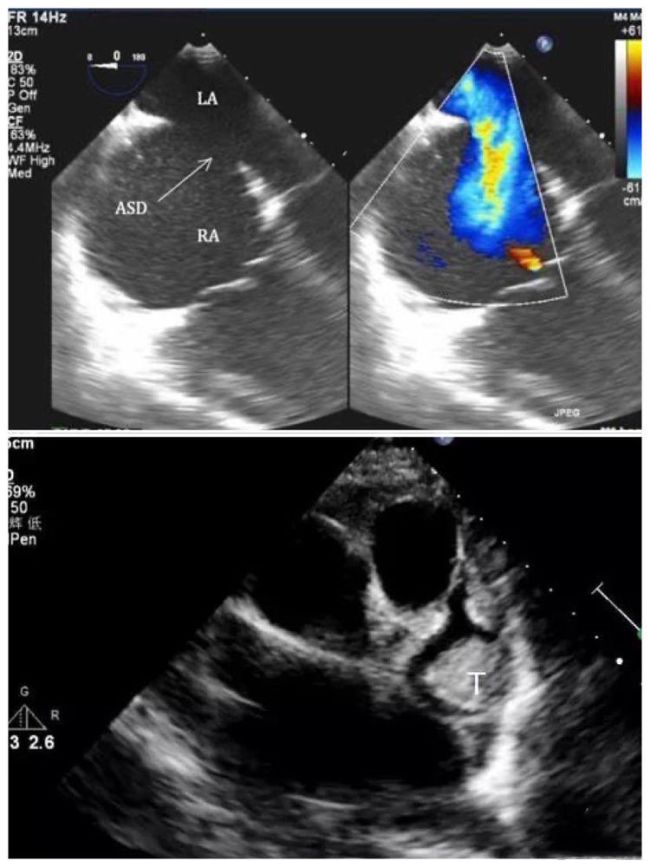

心脏超声检查的新视窗 | 云县人民医院开展经食道超声心动图检查_患者(4)

心脏超声检查的新视窗 ——信阳市中心医院开展经食管超声心动图检查

为心脏手术打开新视窗